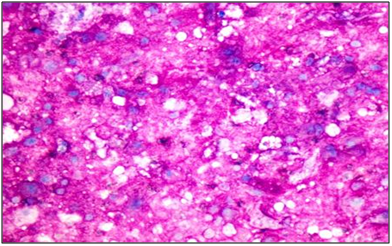

The mass was excised and sent for histopathological examination. Gross examination showed a circumscribed soft tissue mass covered with an elliptical piece of skin with ulceration and sinus formation. Cut surface was firm to hard, vaguely lobulated and variegated with reddish brown hemorrahagic to gelatinous areas (Figure 4). Histopathology revealed a tumour composed of cells arranged in lobulated pattern separated by fibrous septa. The stroma showed myxoid areas and areas of hemorrhage and necrosis. The tumour cells were polyhedral to round with eosinophilic cytoplasm and round atypical nuclei along with physaliphorous cells. Occassional spindle shaped stellate cells and signet ring-like cells were also seen. Physaliphorous cells were large multivacoulated with bubbly appearance of cytoplasm and small inconspicuous nuclei (Figure 5). The cytoplasmic vacuoles were periodic acid Schiff (PAS) positive and diastase sensitive suggesting glycogen deposition (Figure 6). The tumour cells were seen infiltrating the capsule and surrounding soft tissue. The skin overlying tumour showed ulceration and chronic inflammatory cell infiltrate in the dermis. Diagnosis of sacrococcygeal chordoma- NOS was made.